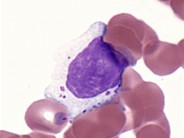

Large granular lymphocytes

A 63-year-old male presented with chronic mild lymphocytosis. Hb 160g/L, WBC 11.3x10^9/L (neutrophil 3.05x 10^9/L lymphocyte 7.35x 10^9/L), Platelet 237x 10^9/L. Blood film showed large granular lymphocytes with abundant cytoplasm and variable number of azurophilic granules. Flow cytometry showed 62% CD3+CD2+CD4+CD5+CD7+CD56+CD57+ T lymphocytes. The CD3+4+:CD3+8+ ratio was 4.30:1.